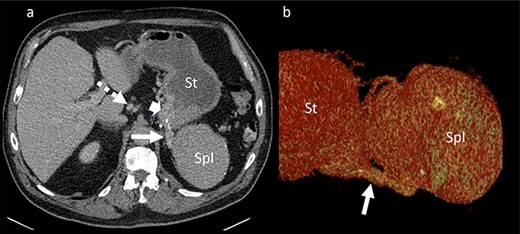

A 65-year-old man with recurrent upper gastrointestinal bleeding was admitted to the Department of Internal Medicine in our institution to identify the source of the varices and therapy. The patient had two episodes of acute upper gastrointestinal bleeding within 1 year, which was treated by sclerosing of gastric varices in a primary hospital. An important note in his medical history was a splenectomy 6 decades before after splenic rupture by blunt abdominal trauma. Endoscopy of the upper gastrointestinal tract showed isolated gastric fundus varices with the absence of oesophageal varices (Fig. 1). To identify the source of the gastric varices, an enhanced computed tomography (CT) of the abdomen was performed and surprisingly demonstrated an 8 cm in diameter mass, mimicking an accessory spleen which

Portal venous phase CT of the upper abdomen (a) with a 3D reconstruction (b); note the gastric varices (arrowhead) and dilatation of short gastric veins (solid arrow) and coronary vein (dashed arrow); St: stomach; Spl: accessory spleen.

was located in the left upper quadrant of the abdomen, nearly adherent to the stomach and a moderate variceal conglomeration in the fundus of the stomach (Fig. 2). Liver cirrhosis or portal vein occlusion and other inflammatory or malignant diseases could be excluded from CT imaging. In addition, a CT scan was able to show clearly that the arterial blood supply of the accessory spleen is derived from the short gastric arteries. Splenic artery and vein could not be delineated. The patient was subsequently presented to our Department of Visceral Surgery. We decided to perform laparoscopic accessory splenectomy to relief the regional hypertension of the short gastric veins. In the operation room, the patient was positioned in right semi-decubitus position. One 12 mm Trocar, two 11 mm Trocars and on 5 mm Trocar were inserted in the left upper quadrant. The accessory spleen was extremely adherent to the diaphragm and retroperitoneal tissue (Fig. 3). After transection of the short gastric vessels with the vessel sealer (Ligasure™, Medtronic, Germany), the spleen was mobilized and removed (Fig. 4). Patient’s postoperative course was completely uneventful, and he was discharged in good health condition on the seventh postoperative day. The diagnosis was confirmed by immunohistologic examination (Fig. 5).